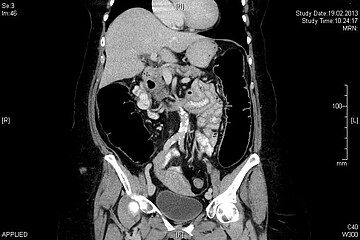

Kommt es zu einem Verschluss des Darmes, spricht man von einem Ileus. Als Ursachen können Verwachsungen (Adhäsionen) oder einzelne Verwachsungsstränge (Briden) vorkommen, welche oft durch vorherige Operationen entstehen. Weiter sind auch Tumore im Bereich des Dick- oder Dünndarms als Verschlussursache möglich.

Die Beschwerden können entweder langsam beginnen und nach mehreren Tagen, selten auch nach Wochen, das volle Bild eines Darmverschlusses zeigen. Genauso können die Beschwerden als plötzlicher und anhaltender Schmerz auftreten ohne weitere Klinik. Die Patientinen und Patienten klagen oft über einen geblähten Bauch, Erbrechen, Übelkeit, assoziiert mit einer mehrtägigen Verstopfung (Obstipation).